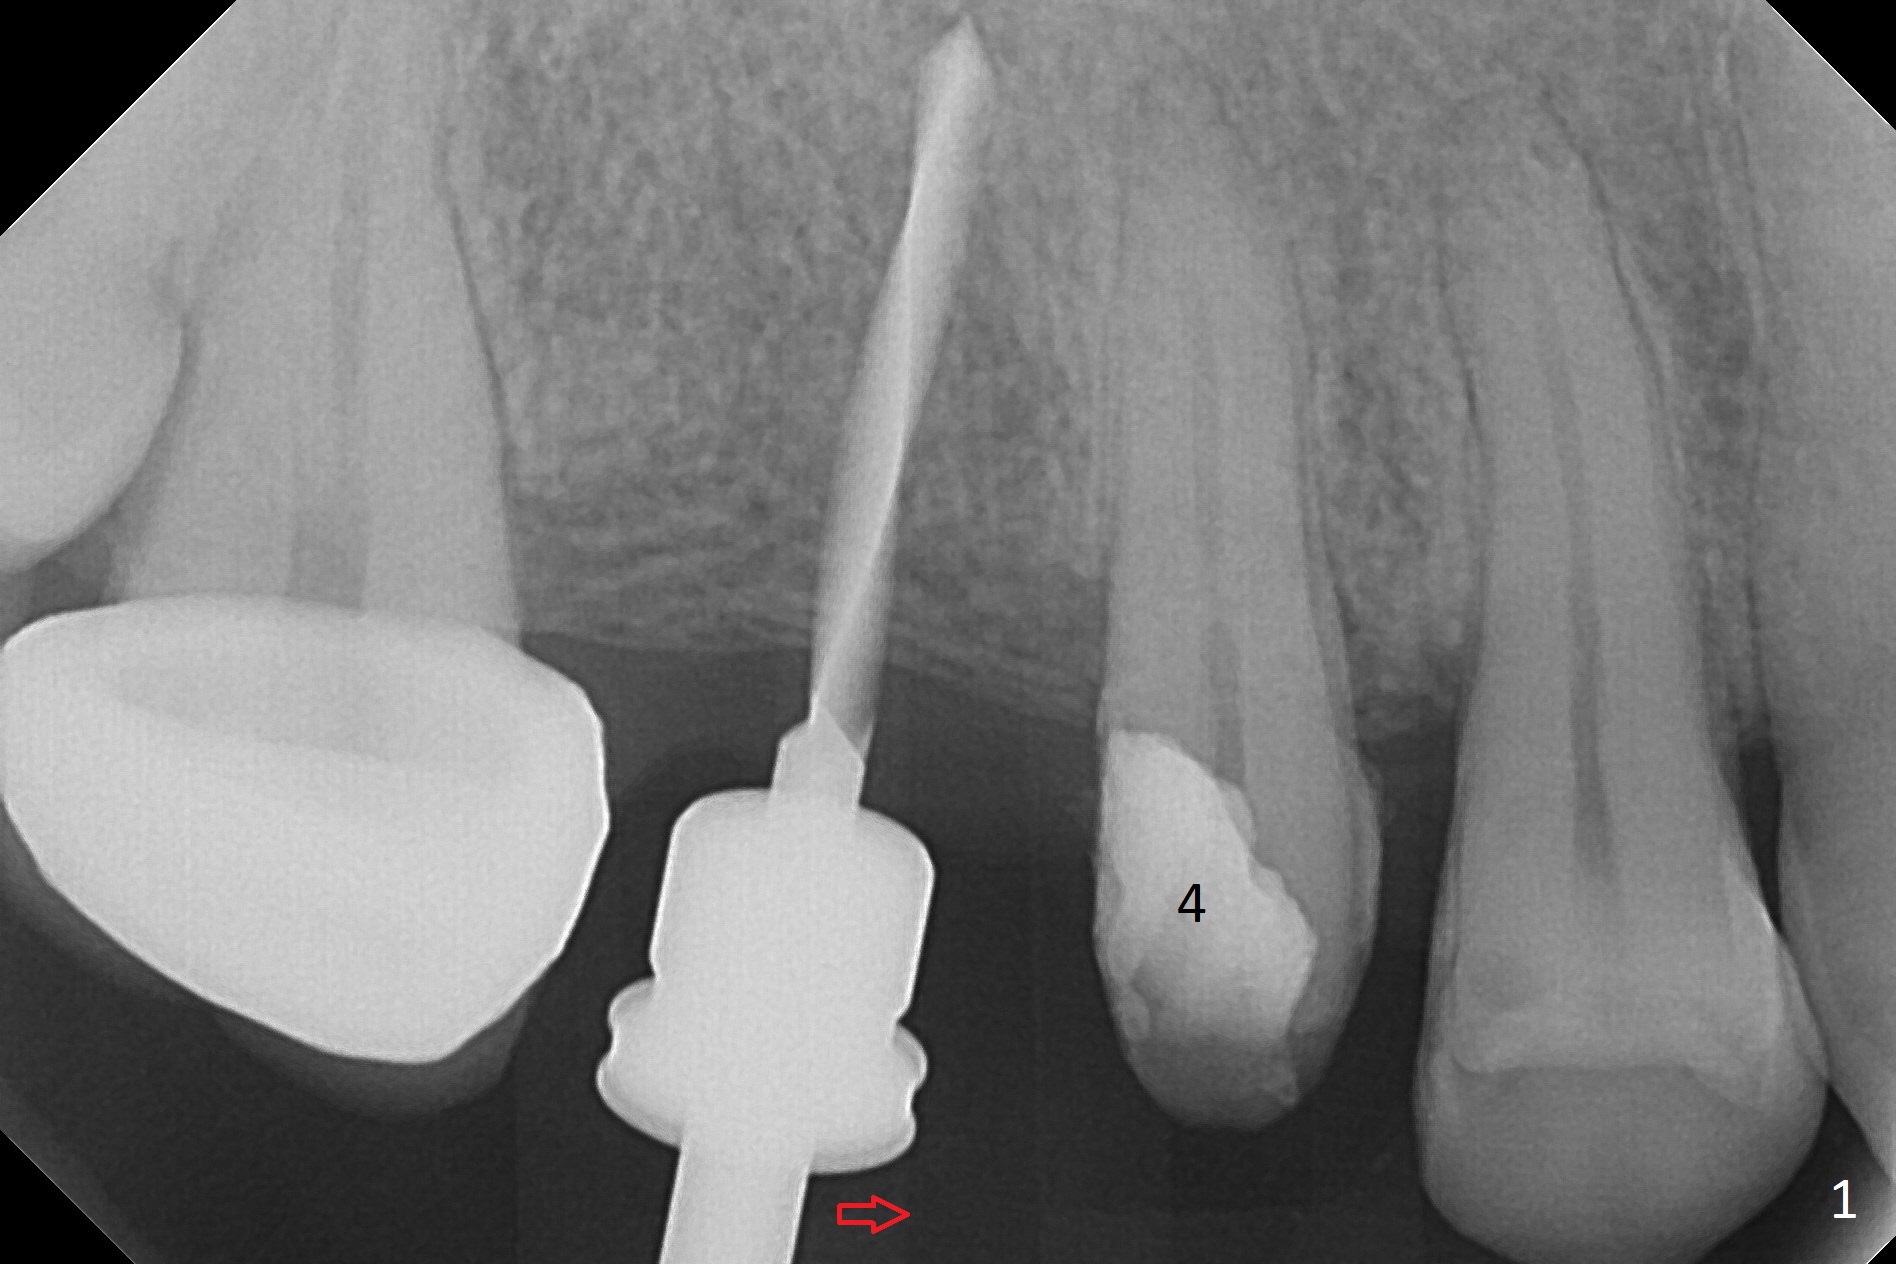

When the bridge is partially removed, the tooth #4 is found to have extensive caries. IRM is placed following carious removal (Fig.1). Magic Split testing shows that the bone density is high (flapless). Osteotomy is initiated by 1.6 mm drill, but the handle of the drill needs to shift mesial (Fig.1 red arrow). When the latter is done, the whole drill (2 mm) needs to move distal (Fig.2 double red arrows). When a 4.5x14 mm drill finishes the osteotomy, it is in the middle of the edentulous space (Fig.3). After use of 5 mm tap, a 5.3x14 mm implant cannot reach the depth (Fig.4,5). Following increase in osteotomy depth from 16 to 18 mm (gingival margin) until 5 mm drill in diameter, the implant placement level is more ideal (Fig.6,7, slightly subcrestal) with insertion torque maintaining at >55 Ncm. The sinus floor (Fig.4 arrowheads) may be penetrated when the osteotomy depth increases (Fig.7 *), but the sinus membrane remains intact.